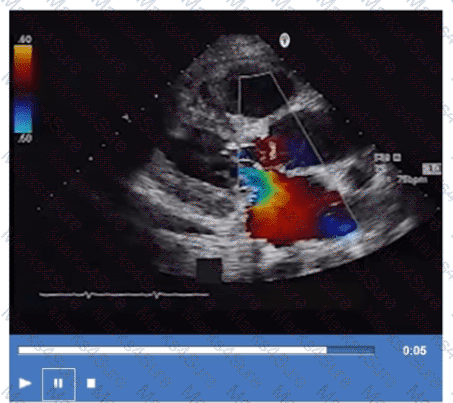

Which Doppler signal is most consistent with significant aortic valve regurgitation?

Which next step is appropriate after obtaining the Doppler signal in this image?